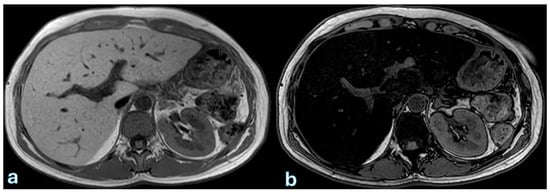

The progression of postoperative fluid collections follows a predictable pattern. Acute fluid accumulations and pancreatic necrosis typically occur within the first week after surgery. By the second to third week, infected necrosis becomes more common, while by the fourth week or later, these collections may transform into pseudocysts or pancreatic abscesses. Identification and characterization of these collections are mostly dependent on cross-sectional imaging, especially contrast-enhanced computed tomography (CECT) and magnetic resonance imaging (MRI).

On CECT, acute fluid collections appear as hypoattenuating areas near the surgical site, often irregular in shape and located adjacent to the pancreatic remnant, anastomotic sites, or nearby vascular structures. In the early stages, these collections are confined by the abdominal fascia and typically lack a discernible capsule.

On MRI, particularly T2-weighted imaging with fat saturation, fluid collections appear hyperintense, though their signal may be inhomogeneous if proteins or hemorrhagic components are present. Hypointense regions within the collection may correspond to blood degradation products, indicating a more complex composition (Figure 2).

In cases of pancreatic necrosis, CECT reveals heterogeneous attenuation due to the presence of nonviable tissue, fat, and hemorrhagic debris [128]. On T2-weighted MRI, necrotic regions appear inhomogeneous, reflecting the mixed composition of necrotic debris and surrounding inflammatory changes. Pancreatic necrosis is often partially or completely encapsulated, forming a well-defined peripheral rim with contrast enhancement on both CT and MRI, suggesting organizing necrosis or early wall formation [73,129]. If the necrotic collection becomes superinfected, the presence of air bubbles within the collection becomes a key diagnostic feature. On CT, air bubbles appear as low-density foci, while on MRI, air appears as signal voids across all sequences, confirming the presence of infection.

Pseudocyst development and pancreatic abscesses are examples of late consequences. On both CT and MRI, pancreatic abscesses appear as fluid collections with a thicker, enhancing wall. The diagnosis is confirmed by the presence of intralesional air, which is pathognomonic for infection. Conversely, pseudocysts are spherical, well-circumscribed fluid collections that seem uniformly hypoattenuating on CT. They are easy to distinguish from solid or necrotic lesions on MRI because they appear hypointense on T1-weighted imaging and uniformly hyperintense on T2-weighted imaging. Debris from the pseudocyst can occasionally be seen at the bottom of the sample as hypointense, irregular material.